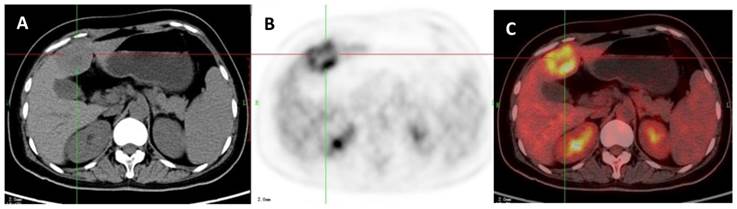

Figure 7

A 53-year-old man with HCC which was proved by liver biopsy. A: Axial non-contrast CT-scan showed a low density lesion in right lobe (cross). B: 18FDG PET image showed almost the same uptake in the lesion (SUVratio=0.98) relative to the liver; C: Axial 18FDG PET/CT fusion image with cross.

The ROC curves and AUC of SUV ratio in younger group are shown in Figure 2. ROC analysis showed that the optimal cut-off value in these patients was 1.17 for SUV ratio and 0.962 for AUC. The younger patients group showed the highest sensitivity and specificity, followed by the older group, and the middle-aged group. Typical 18FDG-PET/CT imaging examples of benign and malignant solitary liver lesions in this group are displayed in Figure 3 and 4. Figure 3 showed a female patient with liver cyst where the SUV ratio was 0.3, and Figure 4 showed a male patient with HCC of which the SUV ratio was 2.1. The ROC curves and AUC of SUV ratio in middle-aged group are shown in Figure 5. ROC analysis showed that the optimal cut-off value in all patients was 1.45 for SUV ratio and 0.650 for AUC. The middle-aged group revealed the lowest sensitivity and specificity. Typical 18FDG-PET/CT imaging examples of benign and malignant solitary liver lesions in this group are displayed in Figure 6 and 7. In Figure 6 from a female patient with liver abscess, the SUV ratio was 4.1, which was much higher than the optimal cut-off value. On the other hand, in figure 7 from a male patient with HCC, the SUV ratio was only 0.98. The ROC curves and AUC of SUV ratio in elderly group are presented in Figure 8. ROC analysis showed that the optimal cut-off value in these patients was 1.25 for SUV ratio and 0.973 for AUC. The elderly group yielded relatively high sensitivity and specificity. Typical 18FDG-PET/CT imaging examples from a patient with benign and malignant solitary liver lesions in this group are demonstrated in Figure 9 and 10, respectively.